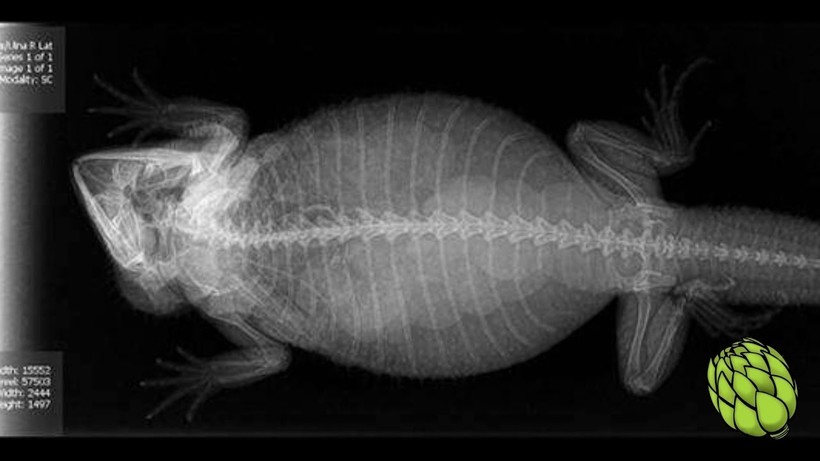

Так выглядит беременность бородатой агамы